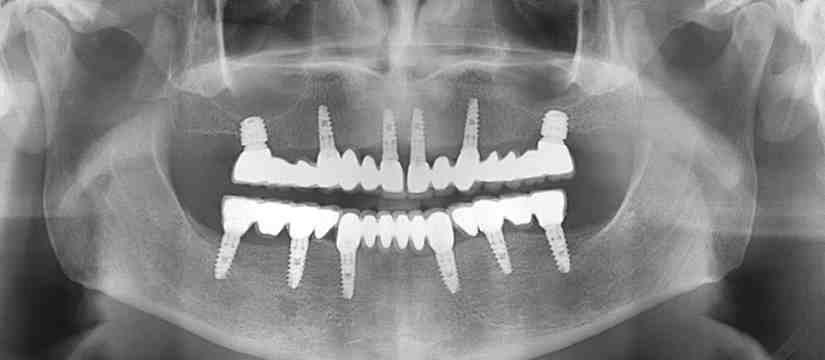

Generally, at least 1mm of bone is needed around the dental implant. When the implant is next to one tooth or another implant, more space is usually needed (2mm to 3mm).

Implant Surgery Your dentist will place a titanium implant in the bone of your jaw, under your teeth. This surgery usually takes about 1-2 hours each time the implant is placed. After completing this step, most dentists will have to wait about 3 months to replace their teeth before the final restoration.

It takes 1-2 weeks for the initial healing process. However, your implant also needs to be “osseointegrated” with your jaw bone. This means that it attaches completely to the bone, making it a natural part of your mouth.

How long does it take for the implant to Osseointegrate to the bone?

Osseointegration is a term used to describe dental fusion of your natural bone implants successfully. This process can take 3 – 6 months to successfully complete the dental implant.